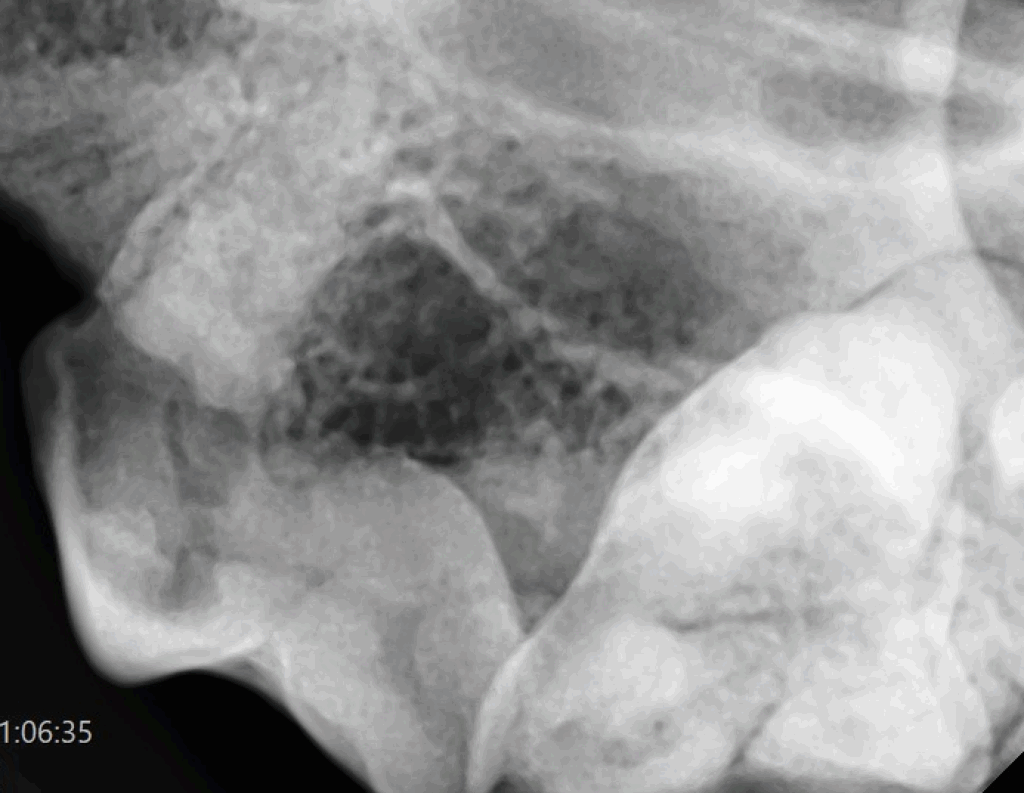

歯冠吸収病巣は、歯の表面(エナメル質・象牙質)が破壊され、徐々に歯が溶けていく病気です。

外からは正常に見えても、レントゲンで初めて異常が確認されるケースが多くあります。

放置すると抜歯が必要になる場合もあり、早期発見と歯科検診(レントゲン)が重要です。

この病気は外から見てわからないことが多いため、歯科健診とレントゲン検査がとても重要です。全身麻酔下での口腔検査には不安を感じる飼い主さまもいらっしゃいますが、歯の健康を守るためには欠かせません。